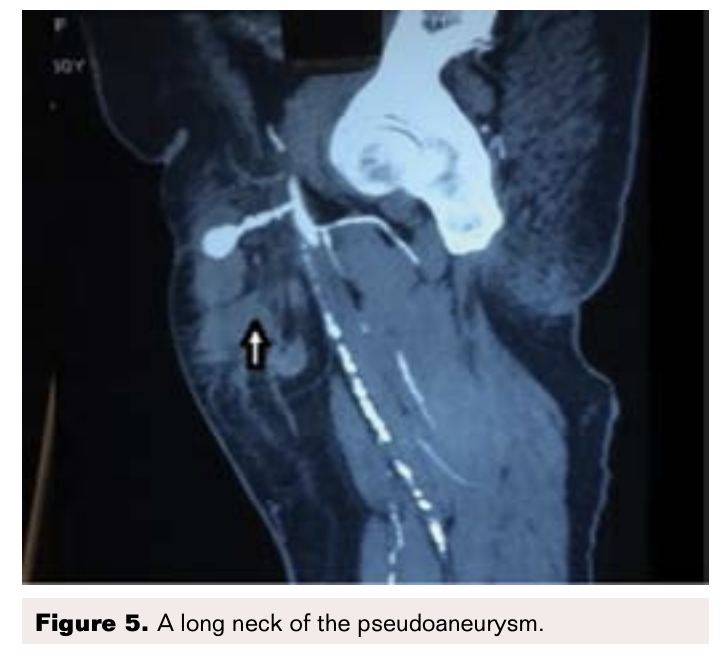

CT Angiogram Findings

A pseudoaneurysm arising from anterior aspect of the right common femoral artery (CFA) just above bifurcation was observed with a sac noted in the subcutaneous space that measured 1.9 x 1.4 cm. A tract from this sac had a length of 2.6 cm and arose from the CFA. A hematoma was noted in the anterior and medial aspect of the thigh in the subcutaneous space adjacent to the pseudoaneurysm (Figures 2-5).